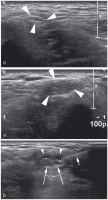

Abbildung 2: Sonographischer Längsschnitt durch den Nervus medianus (Pfeile) am distalen Unterarm eines Probanden mit Darstellung der typischen longitudinal verlaufenden, durch echoreiches Epineurium gegliederten, hypoechogenen Faszikelgruppen. Im Gegensatz dazu diskontinuierliche, eher echoreiche Faszikel der Beugesehnen (Pfeilspitzen).

Abbildung 3a-c: (a) Sonographischer Längsschnitt durch den Nervus medianus (Pfeile) am distalen Unterarm eines Patienten mit Karpaltunnelsyndrom: Abrupter Kalibersprung (Pfeilspitzen) im Verlauf unter dem Ligamentum carpi transversum. (b) Sonographischer Querschnitt durch den Nervus medianus bei einem weiteren Patienten mit Karpaltunnelsyndrom: Deutliche Auftreibung des Nervs im proximalen Verlauf unter dem Ligamentum carpi transversum (Pfeilspitzen) mit einer Querschnittsfläche von 0,21 cm2 (Normwert bis 12 cm2). (c) Sonographischer Längsschnitt (selber Patient) durch den aufgetriebenen Nervus medianus (Pfeilspitzen) mit Darstellung multipler Farbsignale, hinweisend auf eine reaktive Entzündung.